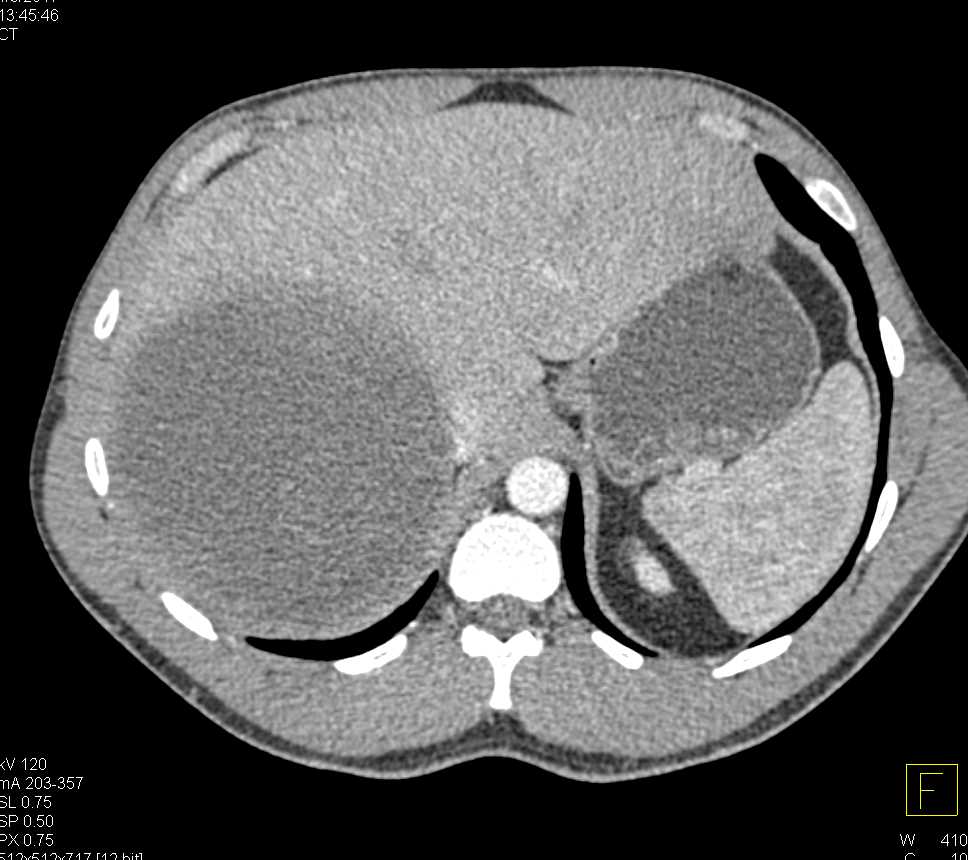

Hepatocellular Carcinoma (Hepatoma) and Bilateral Adrenal Metastases